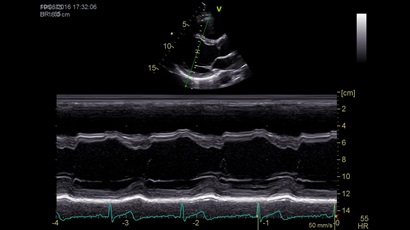

Анатомический М-режим:

Да

M-режим:

• Анатомический М-режим (АММ).

• Криволинейный анатомический М-режим (CAMM).